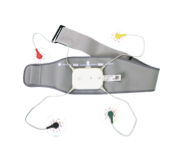

One machine, three uses, measuring three items

Capture each momentary discomfort and protect heart health for the entire family